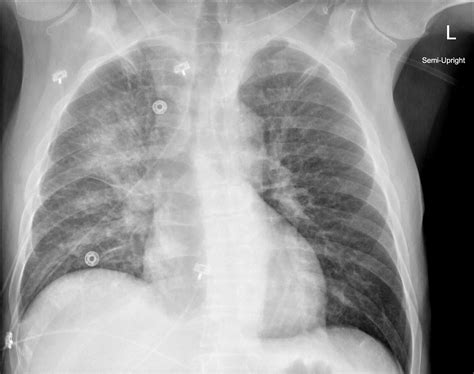

When a patient presents to the emergency department with acute respiratory distress, rapid diagnostic imaging becomes a cornerstone of clinical decision-making. Among the various tools available to physicians, the Pulmonary Edema Cxr (chest X-ray) remains the most frequently ordered and clinically significant diagnostic exam. Understanding the classic radiographic patterns of pulmonary edema is essential for medical professionals, as this condition represents a life-threatening accumulation of fluid in the pulmonary interstitial and alveolar spaces, often secondary to congestive heart failure or other systemic pathologies.

The Pulmonary Edema Cxr is highly sensitive for identifying fluid overload, though it requires a keen eye to differentiate between cardiogenic and non-cardiogenic causes. Radiologists and clinicians look for specific markers that indicate increased capillary hydrostatic pressure or altered vascular permeability. When evaluating a chest X-ray for this condition, the focus is placed on vascular prominence, redistribution of blood flow, and the presence of interstitial or alveolar opacities.

Key radiographic signs often appear in a specific sequence as the severity of the fluid overload progresses. Identifying these early can prevent the escalation to severe respiratory failure. The hallmark appearance is often referred to as "pulmonary congestion," which describes the initial phase of fluid accumulation.

There is a standardized progression of findings visible on a Pulmonary Edema Cxr. Recognizing these patterns allows for a systematic approach to diagnosis. The following findings are commonly documented in clinical reports:

• Cephalization: The redistribution of pulmonary blood flow to the upper lobes, which is one of the earliest signs of increased pulmonary venous pressure.

• Kerley B Lines: These are short, horizontal lines perpendicular to the pleural surface at the lung bases, representing thickened interlobular septa due to interstitial edema.

• Peribronchial Cuffing: This appears as a thickening of the bronchial walls, giving them a "donut" or "cuff-like" appearance on cross-section.

• Pleural Effusions: Fluid collecting in the pleural space, often bilateral but potentially unilateral, commonly seen in congestive heart failure.

• Bat-wing Opacities: In more severe cases, bilateral central alveolar opacities sparing the periphery of the lungs, indicating profound alveolar flooding.